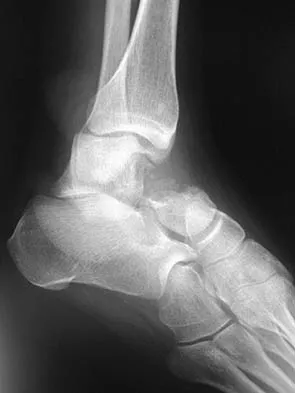

A 57-year-old man has had right ankle pain for the past 10 months following an injury that went untreated. Radiographs are shown in Figures 30a through 30c. Management should consist of

The radiographs reveal a malunited distal fibular fracture with shortening. Because there appears to be an adequate cartilage space within the ankle joint, the role of reconstruction would be to prevent arthrosis and the need for ankle arthrodesis, as well as to decrease symptoms. The treatment of choice is restoration of fibular length, alignment, and rotation with osteotomy plating, and bone grafting as needed. There is no indication for ligament reconstruction of a mechanically stable ankle, and tibial shortening osteotomy will not assist in correcting the deformity. Cast immobilization may assist with improvement of symptoms but will not correct the overall process. Determination of fibular length is best done by comparing the talocrural angle of the injured side with the uninjured side. The goal is to perfectly reduce the talus in the ankle mortise. Marti RK, Raaymakers EL, Nolte PA: Malunited ankle fractures: The late results of reconstruction. J Bone Joint Surg Br 1990;72:709-713. Geissler W, Tsao A, Hughes J: Fractures and injuries of the ankle, in Rockwood CA Jr, Green DP, Bucholz RW, Heckman JD (eds): Rockwood and Green's Fractures in Adults, ed 4. Philadelphia, PA, Lippincott-Raven, 1996, pp 2201-2206.